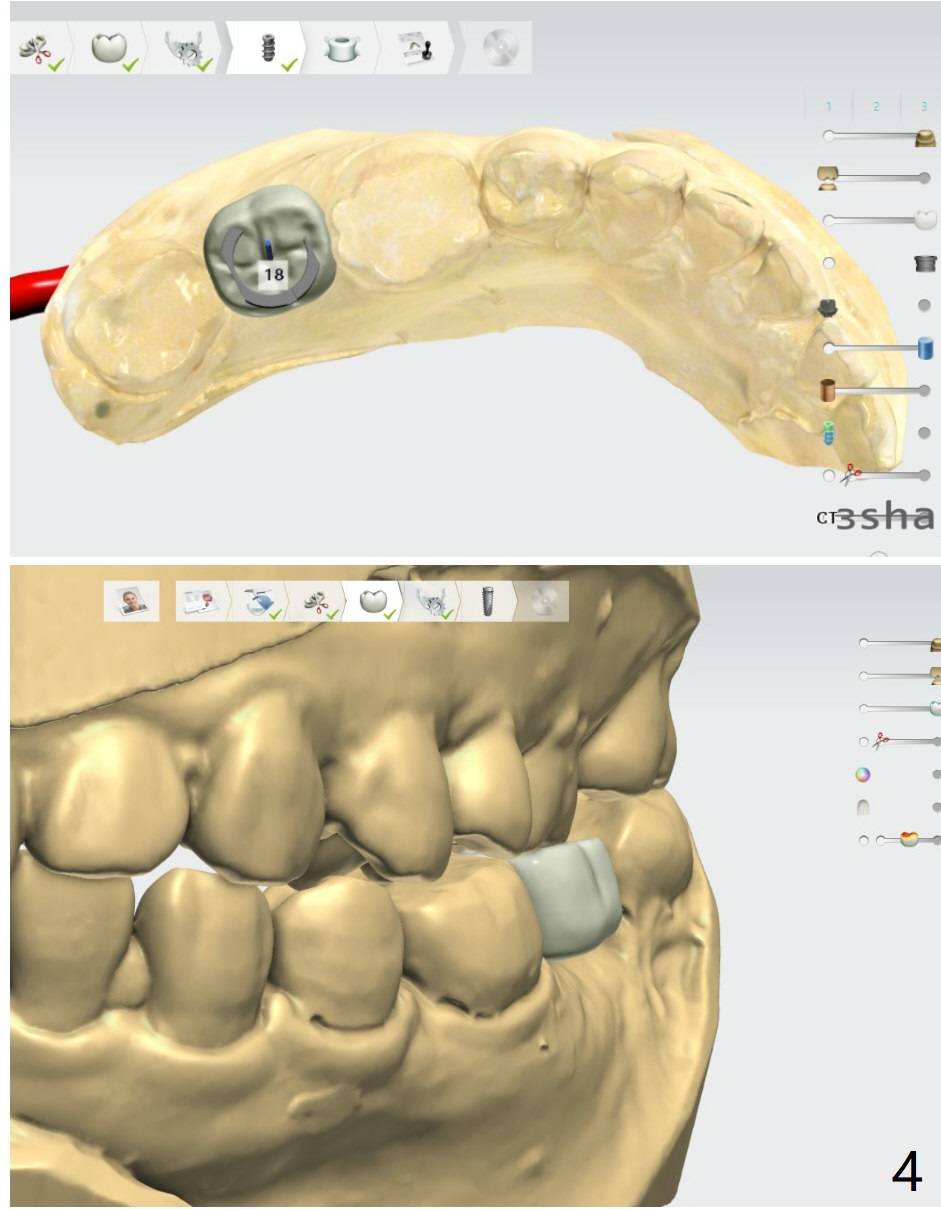

A 25-year-old woman. For sinus lift, 9 mm offset will be used from now on so that DIO sinus approach kit can be applied. Get ready water lift.

Lower Molar

Immediate Implant,

Trajectory II